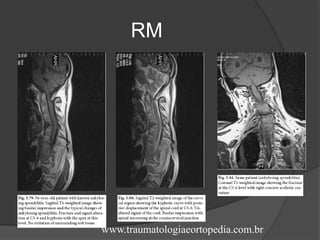

RM

 Osteotomia da coluna cervical:

- Deformidade de queixo no tórax (difícil abrir

a boca e mastigar);

- Indicacões: melhorar aparência, prevenir

subluxações e luxações atlantoaxiais e

cervicais, para aliviar deformação traqueal e

esofágica que causa dispnéia e disfagia;

prevenir irritação dos tratos da coluna

espinal ou tração excessiva das raízes

nervosas o que causa pertubações

neurológicas.

- Hpercorreção deve ser evitada pois s

traquéia e o esófago poderiam ser

excessivamente estirados e se tornarem

obstruídos;